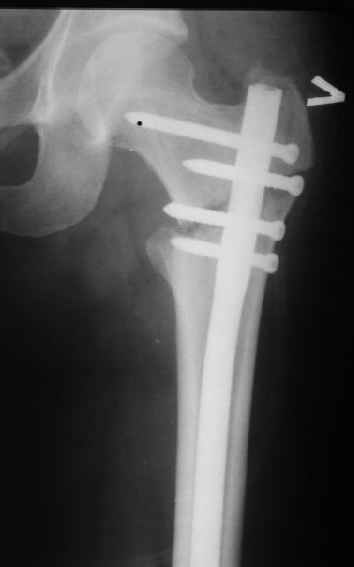

В частности, его возможности при фиксации переломов проксимального отдела бедра - в сравнении с другими, имеюшими лишь по одному статическому и динамическому отверстию и с кондуктором для введения 2 винтов.

Это было года 2,5 назад, мы тогда еще уточняли возможности шинирования с угловой стабильностью гвоздем с поперечным расположением винтов при переломах проксимального отдела бедра. Пациенту не пришлось приобретать намного более дорогой рекон или проксимальный гвоздь. В приложении еще несколько примеров применения того гвоздя при высоких переломах бедра, в том числе с более латеральной точкой входа. Гвоздь изгибаем для этого.